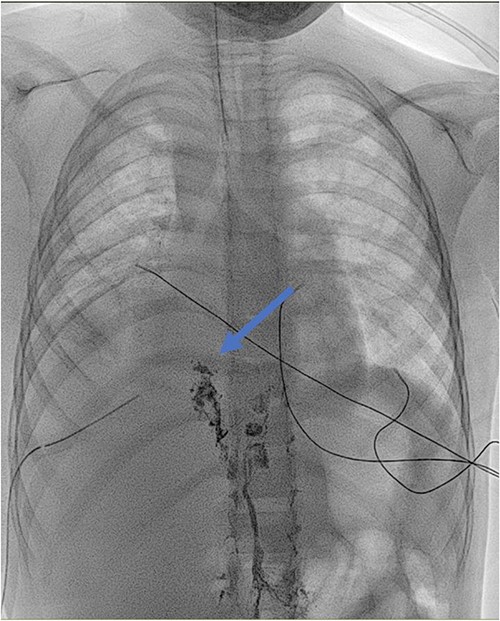

Antibiotic therapy and parenteral nutrition were initiated. In addition, Sandostatin was started at a dose of 1mcg/kg/h. Primary workup lymphoscintigraphy showed no lymphatic leakage or lymphatic abnormalities (Fig. 1). Examinations addressing malignancy and other causes of chylothorax did not reveal any additional pathologic findings. After 14 days of conservative treatment, the patient showed no significant improvement with a pleural fluid production of over 500 cc/24 h. Therefore, it was decided to perform an exploratory thoracoscopy with the injection of indocyanine green. The thoracic duct was visualized during the procedure but showed no active leaks. A pleurodesis was performed. After surgery, there was an improvement with decreased pleural fluid production. Medium Chain Triglyceride (MCT) diet was introduced, and somatostatin was slowly reduced. Unfortunately, after 4 days, the patient reacquired a significant amount of pleural fluid. The thoracic duct was clipped, and a lung biopsy was performed due to the lack of improvement. Clinically, the patient progressed inconsistently with a further episode of vomiting, which resolved spontaneously. The thoracic tube was removed 10 days after the second intervention. Follow-up radiographs showed the return of pleural effusion with the incomplete collapse of the lower lobe. A lymphangiography confirmed the excellent positioning of the clip and could not find any other abnormalities or leaks (Fig. 2). The genetic and anatomopathological study did not show any irregularities. Four months after discharge, the overall condition of the patient was good.

Lymphoscintigraphy: blue arrow indicates axillary lymph nodes, the red arrow shows the inguinal lymph nodes. They are no signs of tracers in the thorax cavity.